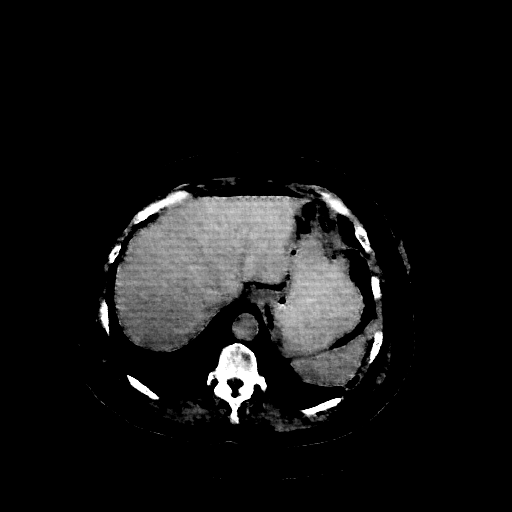

Reconstructed NATIVE CT scan (cycle consistency)

Full window (WL 1023.5, WW 4095 β†’ Low βˆ’1024, High +3071)

Actual HU range: [-1024.0, 690.2]